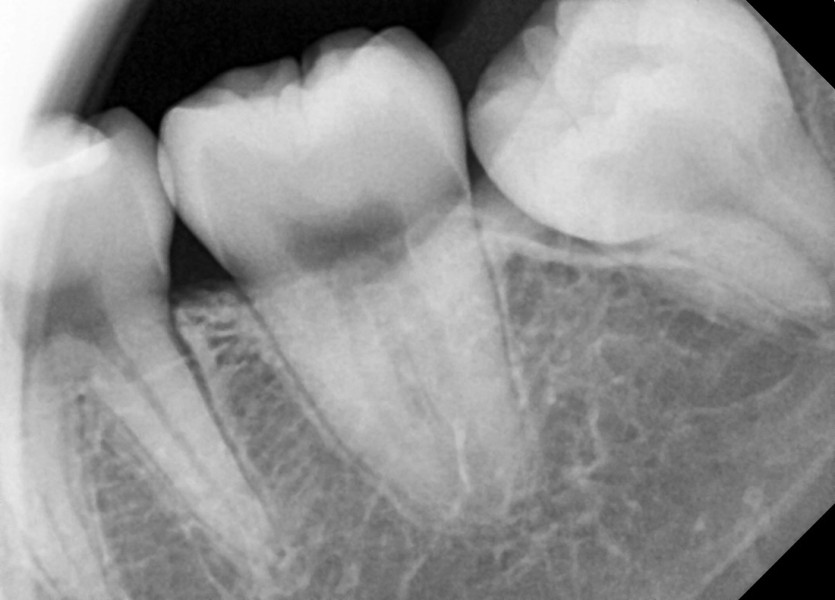

#18,28,38,48 사랑니 발치

구강 외과 전문의가 당일 발치했습니다.